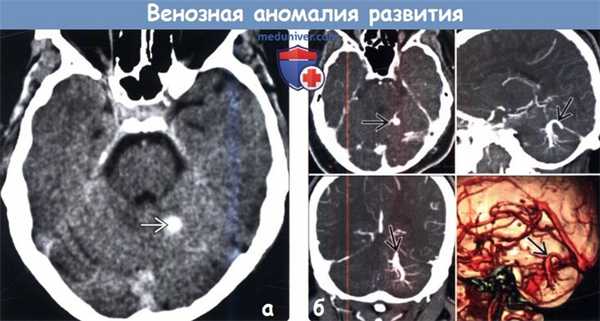

(а) Бесконтрастная КТ, аксиальный срез: хорошо очерченный гиперденсный участок в левом полушарии мозжечка.

(б) КТ-ангиография, аксиальный, сагиттальный и корональный срезы, а также 3D реконструкция у этого же пациента элегантно демонстрируют венозную аномалию развития (BAP).

2. КТ при венозной аномалии развития:

• Бесконтрастная КТ:

о Чаще всего: определяется гиперденсность расширенной «коллекторной» вены; это не патология

о Иногда: Са++ при смешанной кавернозной мальформации (КМ)

о Редко: острое паренхиматозное кровоизлияние (при спонтанном тромбозе дренирующей вены)

• КТ с контрастированием:

о Многочисленные линейные или точечные контрастируемые фокусы:

- Хорошо очерченные округлые/овальные контрастированные участки на серии изображений

- Сходятся на одной расширенной дренирующей вене трубчатой формы

- Иногда визуализируется как линейная структура на одном срезе